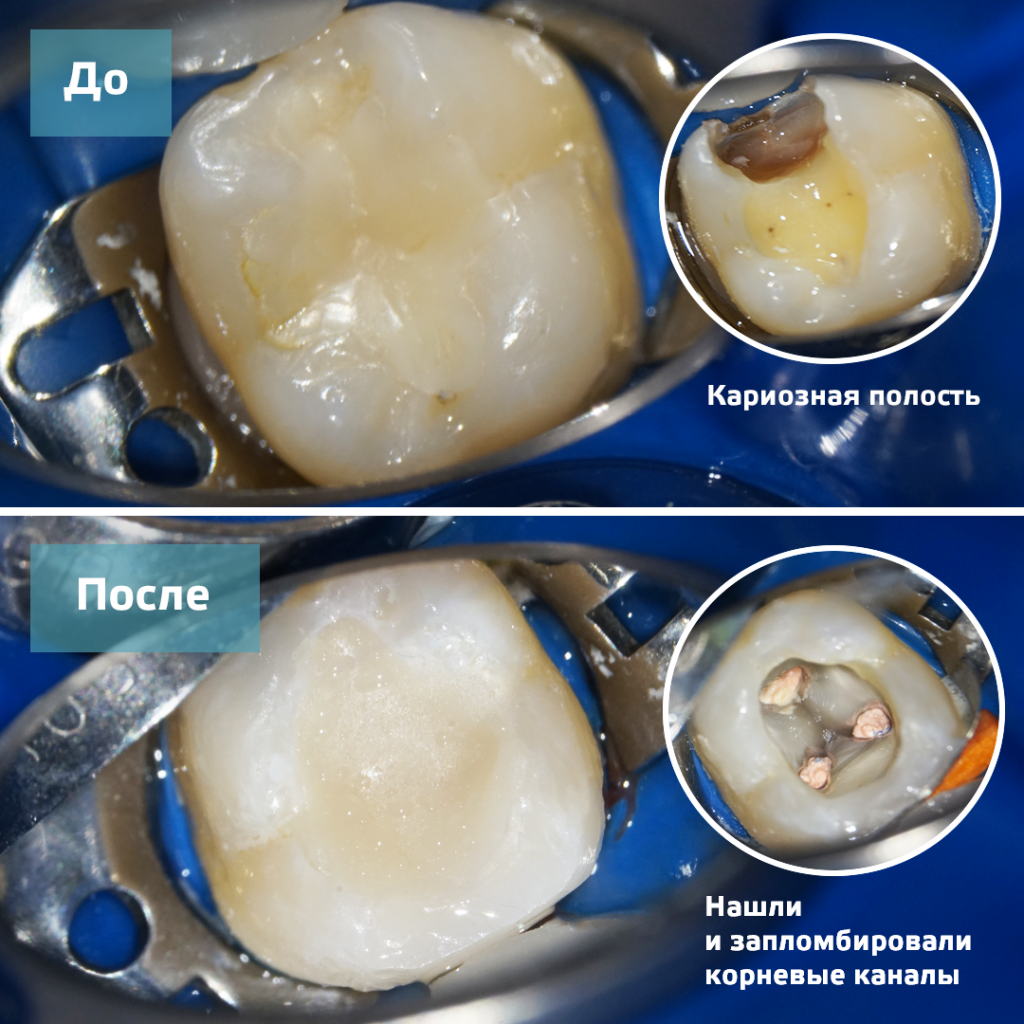

Препарирование кариозных полостей III класса: пошаговое руководство с фото